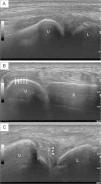

Ultrasound examination revealed distal radio-ulnar synovitis, a hyperechoic band within the distal cubital cartilage, and several hyperechoic spots of the triangular fibrocartilage complex (Fig. 1), compatible with calcium pyrophosphate dihydrate (CPP) crystal deposition (CPPD).

Ultrasound images of the right wrist. (A) Longitudinal view of the distal ulna, with grey-scale grade 2 synovitis of the distal radio-ulnar joint (asterisk). (B) Transverse view of the distal radio-ulnar joint, with an intrahyaline hyperechoic band parallel to the surface of the distal ulnar cartilage (arrows). (C) Several hyperechoic spots with a “punctate pattern” of the triangular fibrocartilage complex (arrow heads). L – lunate; R – radium; U – ulna.